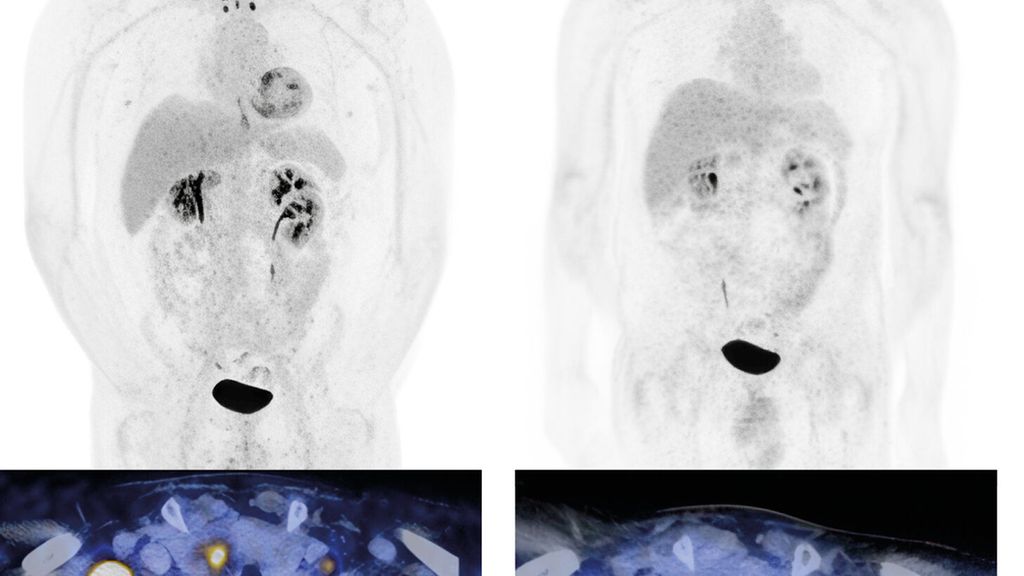

Abb. 1: Urothelkarzinom der Harnblase (initial cT3 cN3 cM0) mit metachron aufgetretener lymphogener Metastasierung. Staging mittels Computertomografie (PET-CT) mit Diagnose der lymphogenen Metastasierung (a, links). Erstes Restaging zwei Monate nach Therapiebeginn mit EV+P (b, rechts). Bildmorphologisch zeigt sich eine Komplettremission. Der Patient befindet sich weiterhin in anhaltender Remission. Bilder und Patient USZ Zürich

Der lokal fortgeschrittene und metastasierte Blasentumor stellt weiterhin eine therapeutische Herausforderung dar. Die Prognose ist trotz jüngster Fortschritte in der Systemtherapie weiterhin meist schlecht. Die Wahl der Erstlinienbehandlung orientiert sich seit Zulassung der Kombinationstherapie mit dem Antikörper-Wirkstoff-Konjugat (ADC) Enfortumab Vedotin (gerichtet gegen Nectin-4) in Kombination mit dem PD-1-Checkpoint-Inhibitor Pembrolizumab (EV+P) an der Tauglichkeit für diese Kombination vs. Nicht-Tauglichkeit.

Das mediane OS konnte mit dieser Kombination signifikant auf knapp 34 Monate im Vergleich zu 16 Monaten mit alleiniger platinhaltiger Chemotherapie ± IO-Erhaltung gesteigert werden. In der Studie waren auch Patient:innen mit schlechterem Allgemeinzustand (bis ECOG 2) und Patient:innen mit reduzierter Nierenfunktion (GFR ≥30ml/min) eingeschlossen. Ein Update mit einem Follow-up von nun 2,5 Jahren zeigt, dass die Patient:innen, die eine komplette Remission (CR) erzielen, auch längerfristig in einer CR bleiben.6